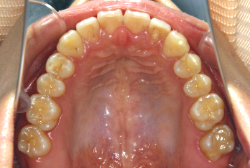

診断の結果、典型的なアングル2級1類の上顎前突です。上下歯列の正中の不一致も見られます。しかし、歯の大きさは平均値に近く、配列の凸凹がそれほど見られません。このまま放置すると、将来的には抜歯を伴う矯正治療を行う可能性が高くなりますが、このタイミングで適切な治療をすると、非抜歯治療が可能かもしれません。

矯正歯科医が着目するのは、奥歯の噛み合わせの位置関係です。前歯の位置にそれなりの差が生じていても、奥歯の位置が正しければそれほど重症という評価にはなりません。このケースの場合は、上下の第一大臼歯の位置関係は、直線的に一致しているタイプでした(矢印が一致)。混合歯列時期の奥歯の位置関係としては、ほぼ正常な状態といえますが、症状から言うと、上の奥歯をもっと後ろに下げてやることができれば、上顎歯列全体に余裕ができるので、凸凹も解消できるし、前歯の傾きを内向きに修正することもできると考えられました。しかしこのまま全体に永久歯が生えきってしまうと、上の前歯が出たままになってしまいますので、生え替わりが完了する前に大急ぎで奥歯を後ろに下げる必要があると判断しました。